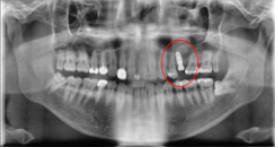

After : 임플란트 후

2021.07.16 / 2021.10.21

임플란트 최종 보철물 식립 후의 사진입니다.

Before / After : 임플란트 전/ 후

2021.07.16 / 21.10.21

임플란트 전, 후의 최종 사진입니다.

치아가 잘 식립된 걸 확인하실 수 있습니다.^^